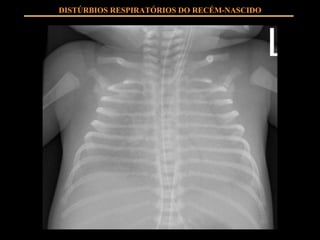

QUADRO CLÍNICO Estigmas de prematuridade Taquipnéia Esforço respiratório Cianose Hipoventilação DISTÚRBIOS RESPIRATÓRIOS DO RECÉM-NASCIDO